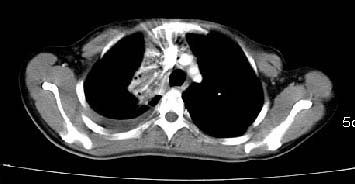

以下是引用zjzjr在2007-3-15 13:31:00的发言:[br]支持楼主诊断.右侧中央型肺癌伴右上叶节段性肺不张、胸腔积液、纵隔淋巴结转移。

以下是引用zyx168在2007-3-15 17:05:00的发言:[br]右侧中央型肺癌伴右上叶节段性肺不张、胸腔积液、纵隔淋巴结转移。